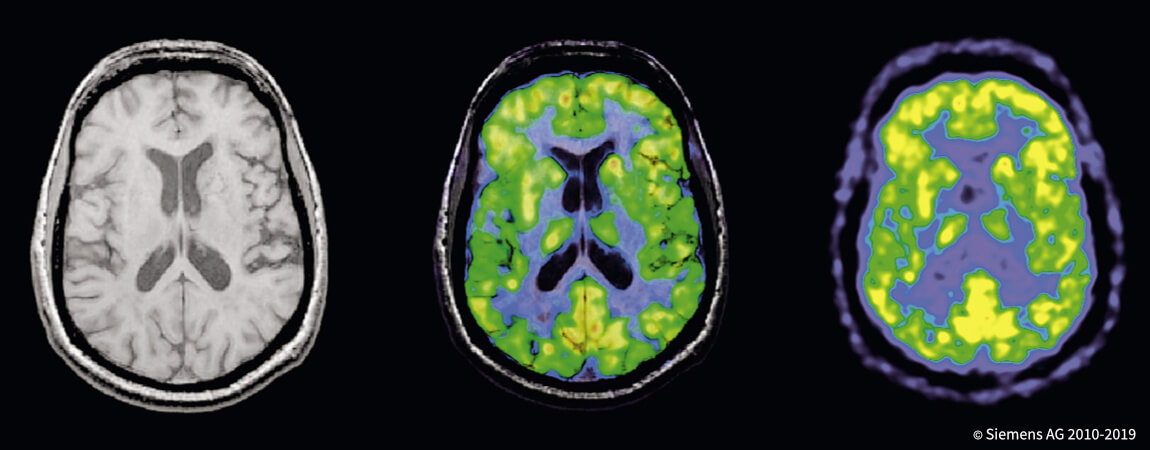

- _Все методы томографии

- _Ядерная медицина: сцинтиграфия скелета, ПЭТ-КТ